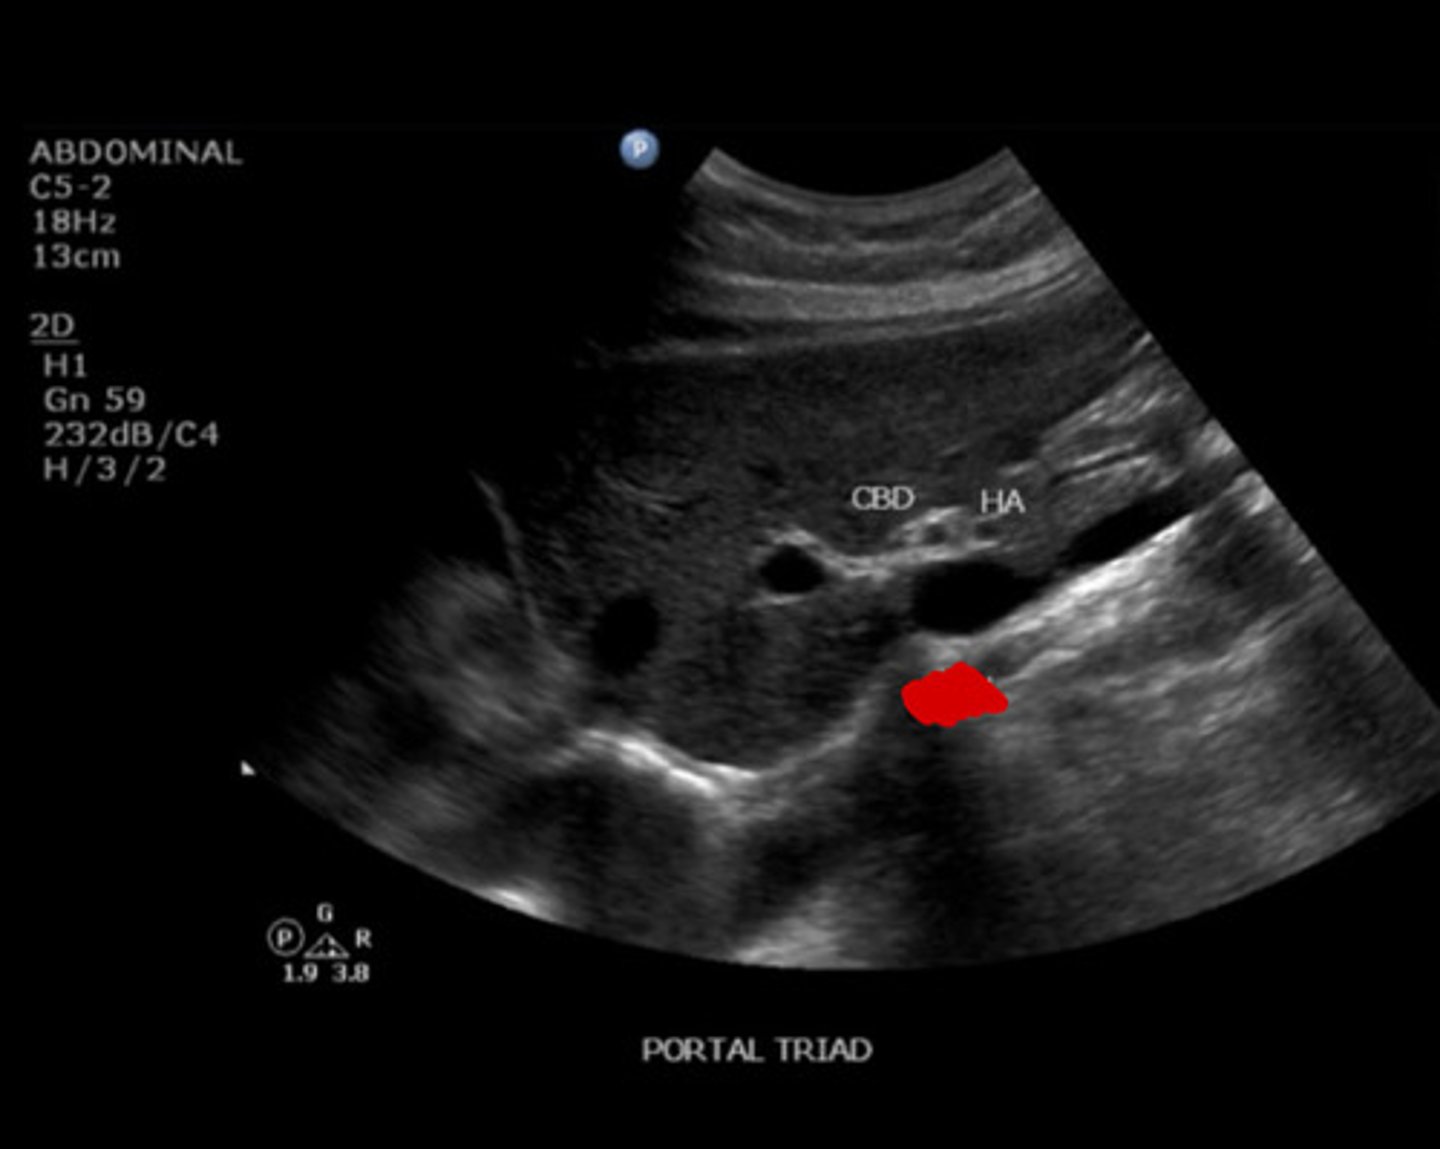

11

New cards

CBD

Identify the following;

<p>Identify the following;</p>

12

HA